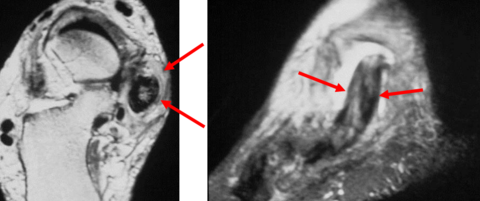

| What does the arrow show? What could this be? | Teardrop-shaped hypointense lesion in third interspace. Could be morton's neuroma |